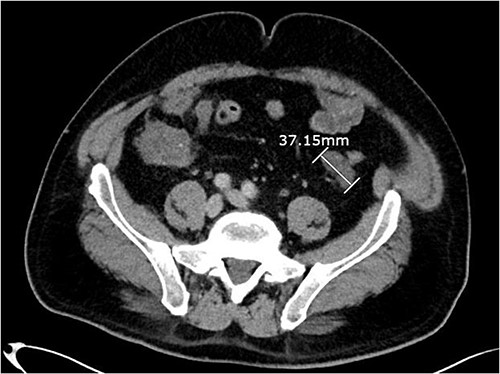

Axial CT abdomen with contrast demonstrating a peritoneal deposit posterior to the descending colon in the left iliac fossa, measuring 37.15 mm.